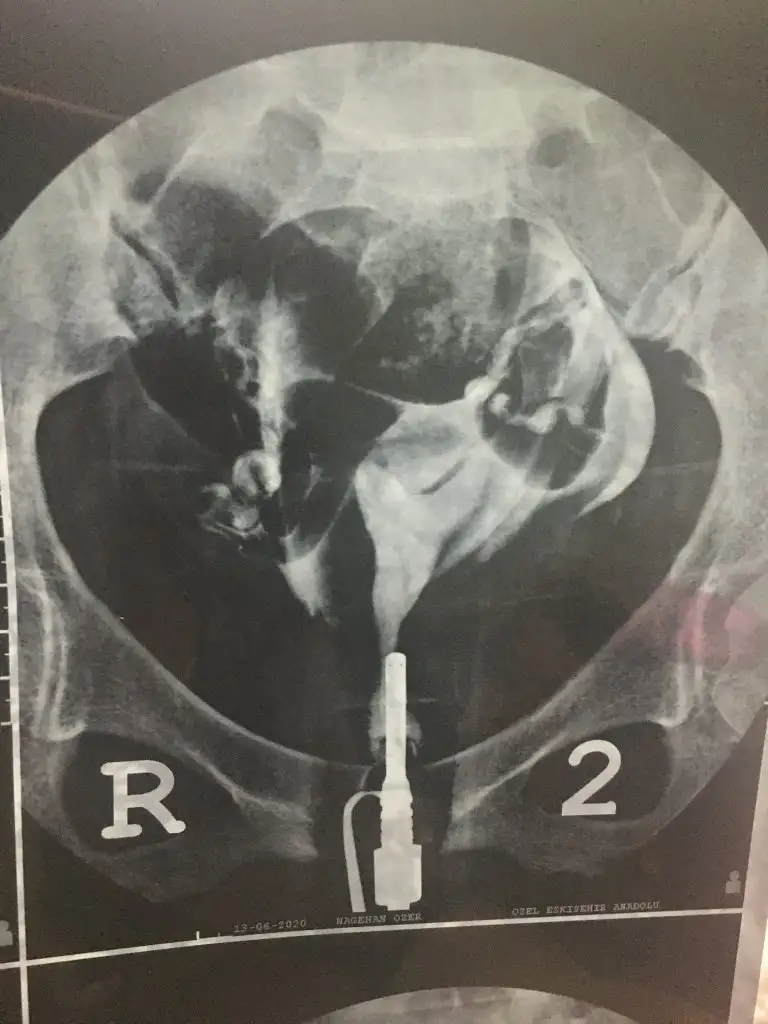

kendi filmimle karşılaştırcam merviş şimdi filmi ama seninkine benziyor benm rahmimde. Atayım mı sana da? Benm 1.56 amh çok yüksek değil yaşına göre dedi daktır o yüzden sordum etkiliyor mu amhı diye. Kolay bi operasyon mu?BankacI26 bak ilk mesajda var benim hsg. Benim amh yazın 0.64tü az olduğu için düşük riskini alamadık. Bu şu an gebeliğe engel değil ama bu çıkıntı çizik atılarak giderilirse embriyo daha iyi tutunuyo.

Buda benim rahmim. Merviş konuyla alakası yok ama dua grubu açta okuyalım yaKolay valla. Şipşak. At bakiim bekliyom

Canım seninki daha çıkıntı sanki ya. Bence riske atma.Buda benim rahmim. Merviş konuyla alakası yok ama dua grubu açta okuyalım ya